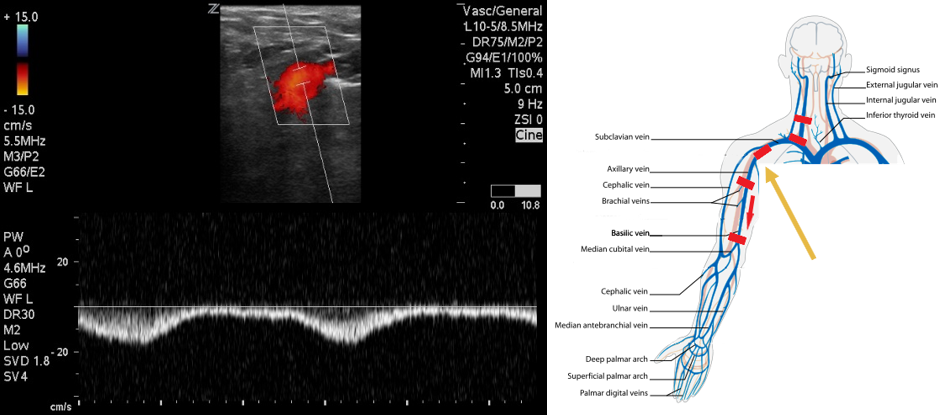

- Follow the IJ to the confluence with the SCV where they form the brachiocephalic vein. Compression in this region will not be possible. Use color flow to evaluate for filling defects and pulsed wave Doppler to evaluate for flow patterns. Absent or monophasic patterns are abnormal. Biphasic or triphasic flow is normal.

- Figure 4. Pulsed wave Doppler over subclavian vein demonstrates biphasic flow.

- Identify the subclavian vein as it crosses from the axilla. This area can be difficult to compress. Use color flow in long axis to identify filling defects. Use pulsed wave Doppler to identify normal versus abnormal flow patterns.

- Figure 5. Pulsed wave Doppler over axillary vein demonstrates biphasic flow.